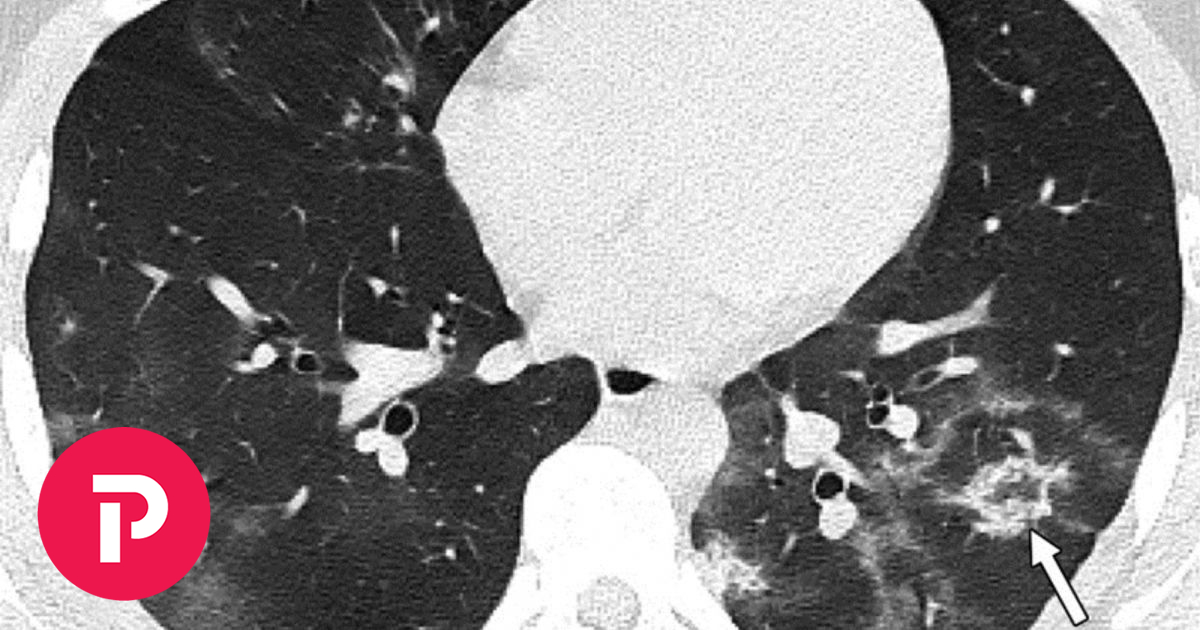

Covid-19:Εικόνες– σοκ από βλάβες σε πνεύμονες υγιών ανηλίκων (photos)

Ο Γκίκας Μαγιορκίνης, καθηγητής επιδημιολογίας και μέλος της επιτροπής εμπειρογνωμώνων, μέσα από μία ανάρτηση στο Facebook επισήμανε τις βλάβες που μπορεί να προκαλέσει ο κορωνοϊός στους πνεύμονες, ακόμα και στους νέους χωρίς υποκείμενα νοσήματα. Ο καθηγητής, δημοσιεύοντας φωτογραφίες από αξονικές τομογραφίες νέων κάτω των 18 ετών, χωρίς υποκείμενα νοσήματα ή ανοσοκαταστολή, έκανε έκκληση για περισσότερους […] The post Covid-19:Εικόνες– σοκ από βλάβες σε πνεύμονες υγιών ανηλίκων (photos) first appeared on Lykavitos.gr.

Μαγιορκίνης: Οι βλάβες που αφήνει ο κορωνοϊός σε ανεμβολίαστους ανήλικους

Μαγιορκίνης: Ο καθηγητής κρούει τον κώδωνα του κινδύνου για όσους δεν έχουν εμβολιαστεί.